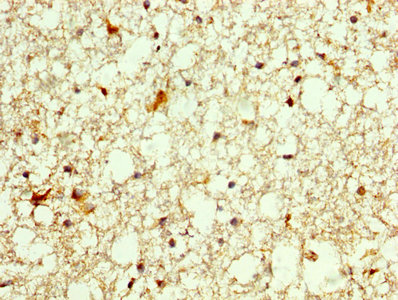

IHC image of CSB-PA017299LA01HU diluted at 1:250 and staining in paraffin-embedded human brain tissue performed on a Leica BondTM system. After dewaxing and hydration, antigen retrieval was mediated by high pressure in a citrate buffer (pH 6.0). Section was blocked with 10% normal goat serum 30min at RT. Then primary antibody (1% BSA) was incubated at 4°C overnight. The primary is detected by a biotinylated secondary antibody and visualized using an HRP conjugated SP system.

IHC image of CSB-PA017299LA01HU diluted at 1:250 and staining in paraffin-embedded human pancreatic cancer performed on a Leica BondTM system. After dewaxing and hydration, antigen retrieval was mediated by high pressure in a citrate buffer (pH 6.0). Section was blocked with 10% normal goat serum 30min at RT. Then primary antibody (1% BSA) was incubated at 4°C overnight. The primary is detected by a biotinylated secondary antibody and visualized using an HRP conjugated SP system.